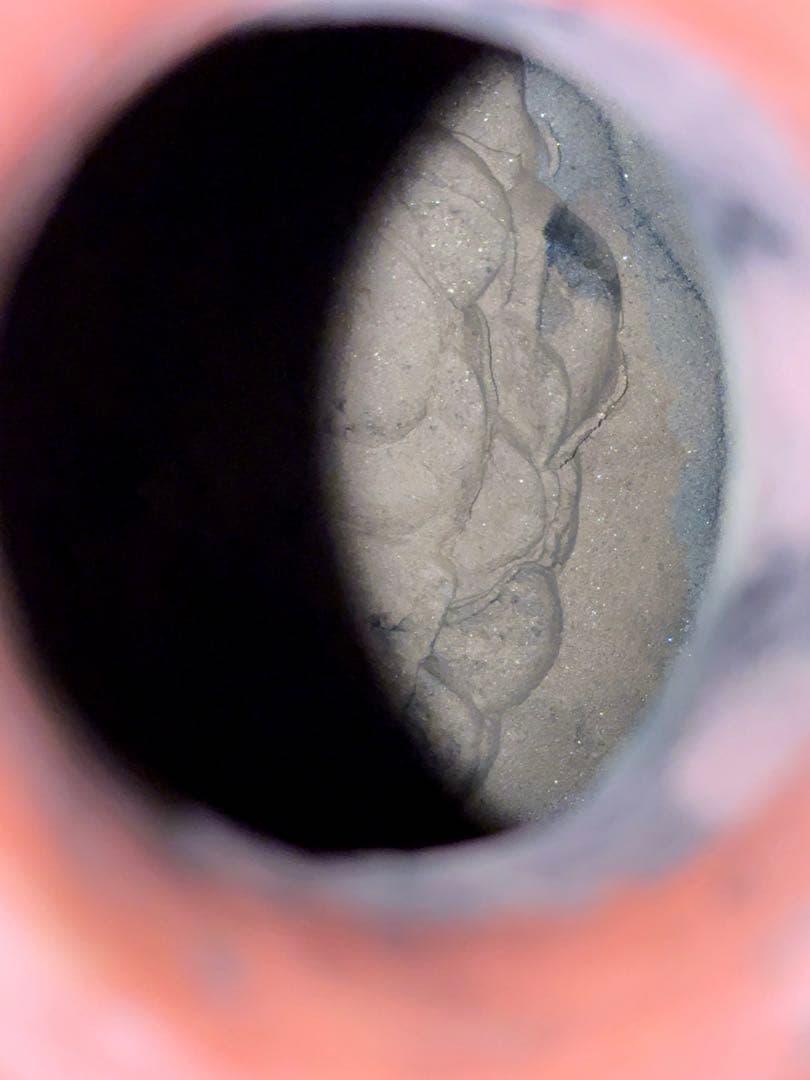

高さ13.3cm、554g可能な限りすぐ発送します(郵便局開局の平日)。 基本的には定形外、大きい場合はレターパックにての発送です。定形外は平日のみ郵便局が配達します。 多忙のため管理番号のお知らせ等、必要な時以外は基本的に無言取引となります。メッセージ等も不要です。 値段は送料(着払いの場合を除く)・梱包費用込ということをご考慮ください。。フランスアンティーク シーリングスタンプとペーパーナイフのセット。清朝 大清康熙年製 青花 大皿 中国美術 茶道具 煎茶道具 清時代 骨董品。欧州伝統紋章デザイン ピンバッジ2種 七宝調 ラペル 革ジャン ルードギャラリー。【t】アンティークベア アンティークテディベア ハーマン。gault house ゴーハウス アパルトマン 大。シュタイフ ヴィンテージ Jocko チンパンジーお店の情報